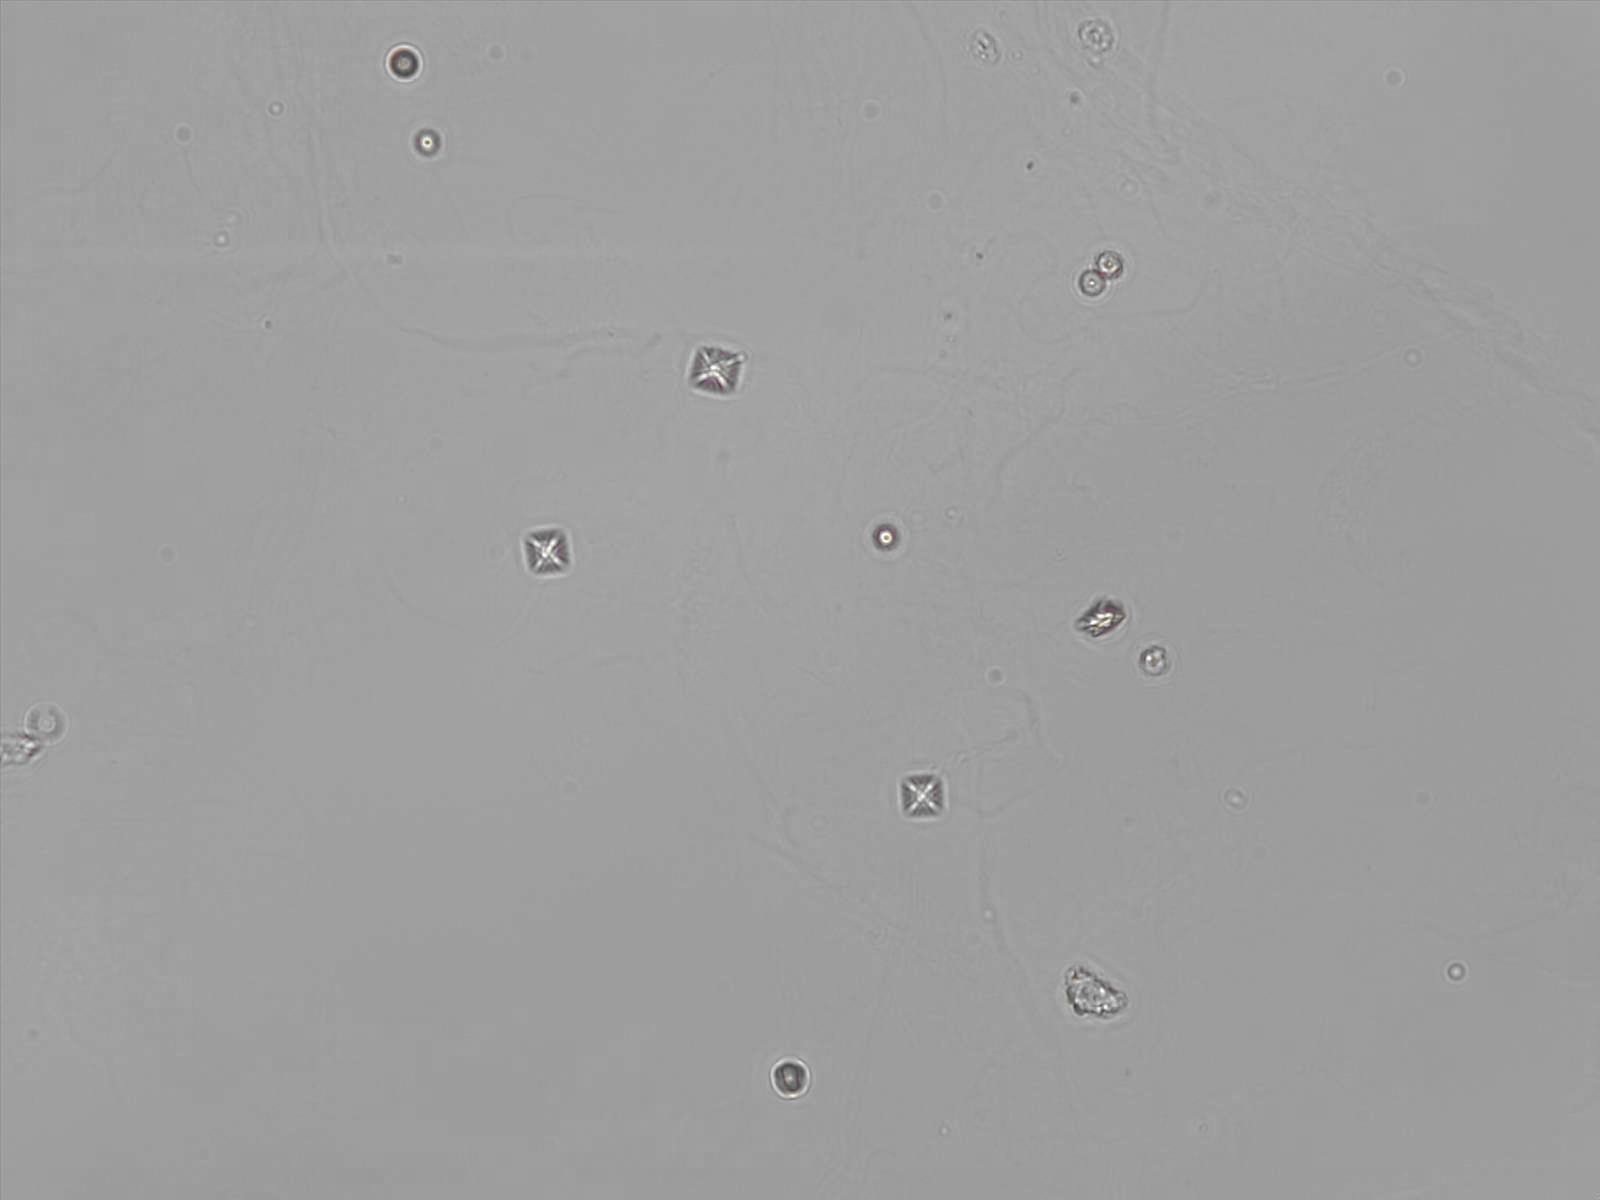

CaOx - Octahedraal

Synoniemen: Weddeliet, CaOx, CaC₂O₄·2H₂O

Calciumoxalaat dihydraat kristallen hebben karakteristieke bipyramidale of prismatische vormen. Onder de microscoop verschijnen ze vaak als envelop-vormige structuren, met een duidelijke en symmetrische morfologie. De grootte van de kristallen kan sterk variëren.

De aanwezigheid van calciumoxalaat is zelden klinisch relevant, maar kan wel een aanwijzing zijn voor de aanwezigheid van nierstenen. Ze ontstaan ook vaak in opgeslagen, oude urine. Elke vorm van calcium oxalaat is polariserend.

Overzicht